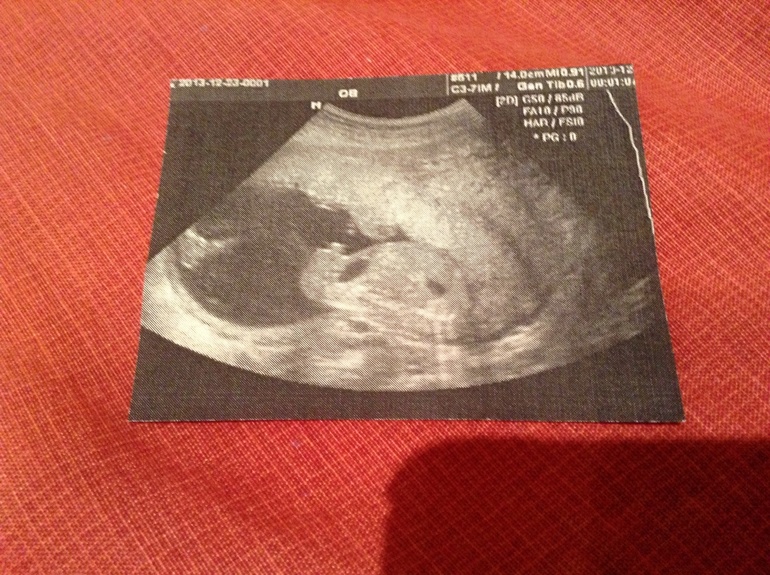

Вот тут слева нога, в центре пипка:)

Здесь вроде все причандалы - в центре "ракета":)